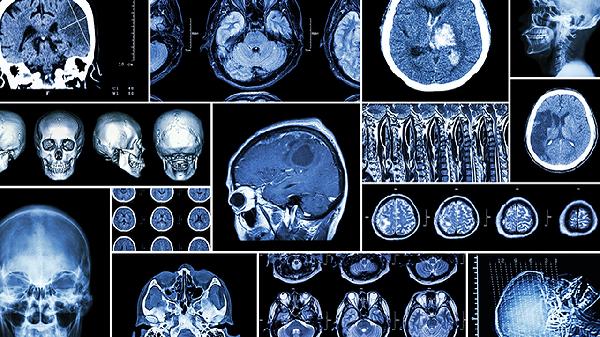

CT检查已经成为现代医学诊断的重要手段,但每次走进那个圆环状的机器时,心里难免会犯嘀咕:这辐射会不会对身体造成伤害?今天我们就来聊聊这个让人又爱又怕的检查项目。

一、CT检查的辐射到底有多大?

1、辐射量的直观对比

一次胸部CT的辐射量大约是7mSv,相当于自然环境中2-3年的本底辐射。而一次跨大西洋航班的辐射量约为0.1mSv,这样对比来看,CT检查的辐射量确实较高,但仍在安全范围内。

2、不同类型CT的差异

头部CT的辐射量相对较低,约2mSv;而腹部或盆腔CT则可能达到10mSv。增强CT由于需要多次扫描,辐射量会更高一些。

3、与常规X光的比较

一张胸片的辐射量仅0.1mSv,相当于胸部CT的1/70。但CT提供的诊断信息要丰富得多,这是辐射与诊断价值的权衡。